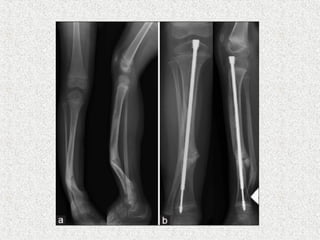

ļ‚ž Sofield & Millar

ļ‚” Multiple osteotomies

ļ‚” Realignment

ļ‚” Medullary nail-solid

ļ‚ž Indication

ļ‚” Deformity correction

ļ‚” Prophylaxis